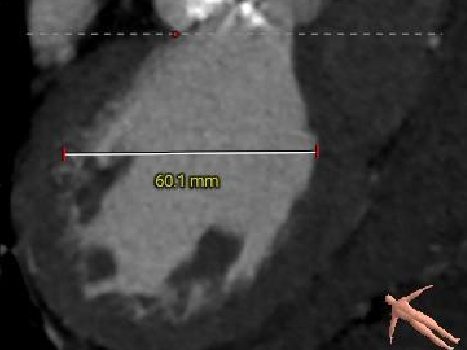

术前CT分析(76岁,女性)

▶ Type1型二叶式主动脉瓣(L-R),瓣叶增厚,重度钙化,钙化分布不均匀,无窦钙化延申至STJ以上,LVOT偏直筒型。

▶ 左右冠脉开口高度尚可,左窦瓣叶切线测量距离>冠脉开口下缘到根部距离。

▶ 心室腔内径尚可,心室壁厚度可,心尖尚可。

▶ 瓣环水平夹角72°,横位心,主动脉弓角、弓距尚可。

▶ 外周血管内径可,血管走行尚可,右侧股动脉高分叉,左侧股动脉低分叉,腹主动脉见钙化附着。

主动脉根部测量